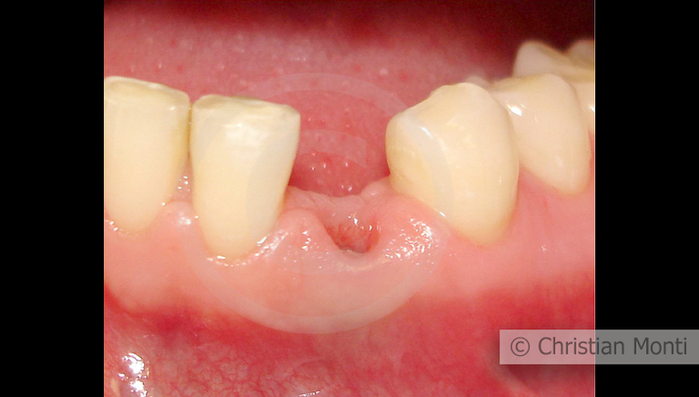

EDENTULIA SINGOLA

Impianto in sostituzione di un canino deciduo